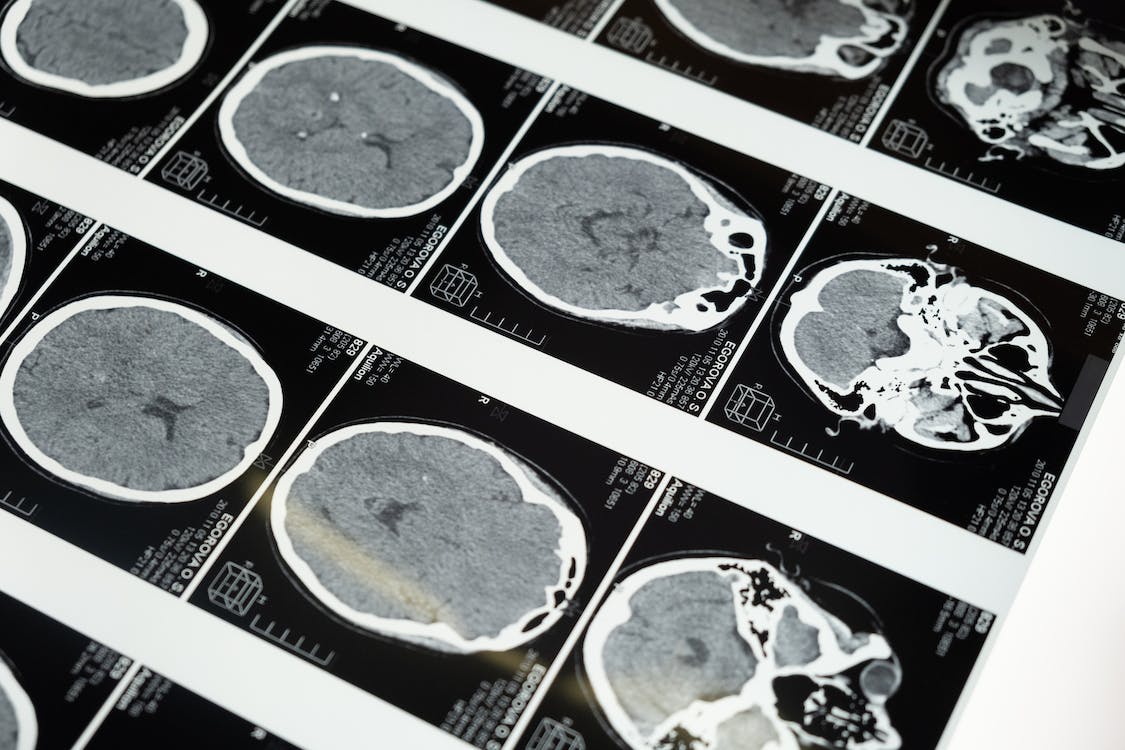

وتمكن الباحثون في مركز UT Southwestern الطبي في الولايات المتحدة من عزل تدفق الدم إلى دماغ خنزير تم تخديره بالكيتامين، بينما حافظت خوارزمية محوسبة على ضغط الدم الضروري وحجمه ودرجة حرارته والمواد المغذية التي يحتاجها العضو.

وأفاد فريق أطباء الأعصاب أن نشاط الدماغ شهد تغيرات طفيفة خلال فترة خمس ساعات، على الرغم من عدم تلقي أي مدخلات بيولوجية من بقية الجسم.

وخلص الباحثون في دراستهم التي نشرت في وقت سابق من هذا الشهر إلى أنه "باستثناء زيادة أكسجة أنسجة المخ عند مكملات الأكسجين، والتغيرات المعتدلة في الضغط داخل الجمجمة، ارتبط هذا النظام بمستويات قريبة من الأصلية من المعلمات الفسيولوجية الدماغية مثل الضغط داخل الجمجمة، وتشبع الأنسجة بالأكسجين ودرجة الحرارة".